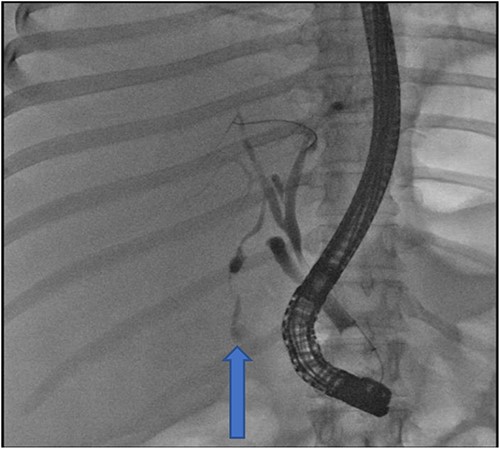

At our facility, ERCP was done. The bile duct was cannulated with 0.035 wire-guided sphincterotome. Cholangiogram showed normal caliber biliary tree with one filling defect in the distal CBD and contrast leak from duct of Luschka to the gall bladder bed (Fig. 1). There was no contrast leak from the cystic duct stump (Fig. 2A). Standard sphincterotomy was performed and a single mulberry stone was removed using stone retreival balloon and double pig tail biliary plastic stent was placed into the RHD and good bile flow was achieved post procedure (Fig. 2B).

Fluoroscopy image indicating bile leak from type 2 duct of Luschka.

(A) First fluoroscopic image shows evidence of no bile leak from cystic duct stump as indicated by the arrows; (B) second fluoroscopic image shows a stent placed into the RHD.